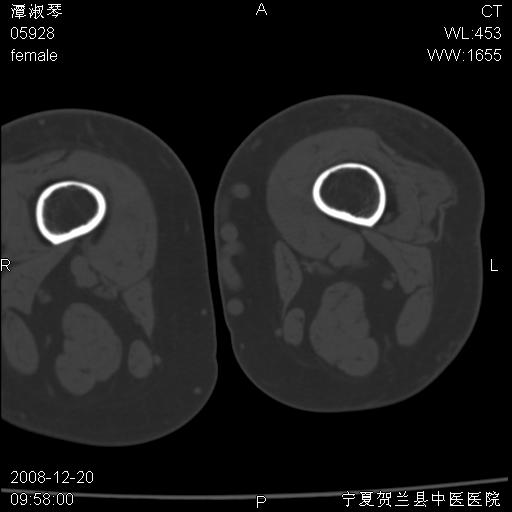

标题: CT17526:请各位看看是啥?

内生软骨瘤?骨梗死?

考虑内生软骨瘤可能性大

考虑-----骨梗死+退变

支持骨梗死,退行性骨关节病,膝关节积液.

考虑骨梗死可能性大

支持骨纤或内生软骨瘤或骨梗死,退行性骨关节病,膝关节积液.

骨梗死可能性大

左股骨下段骨梗死。双膝退变。

支持:内生软骨瘤或骨梗死!另:退行性骨关节病,膝关节积液。

左胫骨下端松质骨及髓腔内可见点片状高密度灶,骨皮质无明显膨胀及变薄。病变范围较长。支持骨梗死,退行性骨关节病,膝关节积液